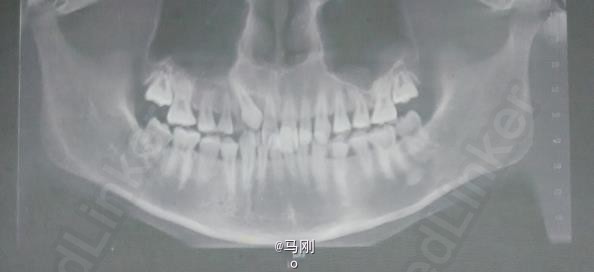

查体 辅查

专科检查:右侧乳尖牙滞留,13腭侧粘膜轻度肿胀。CBCT检查:13位于腭侧。